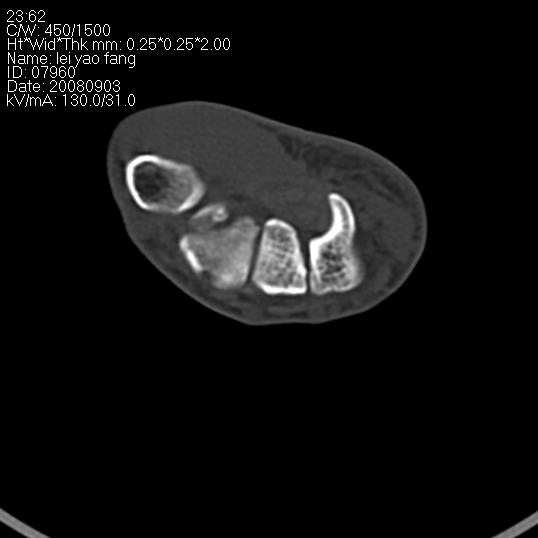

以下是引用杀毒软件在2008-9-4 17:41:00的发言:[br]考虑----舟骨囊肿